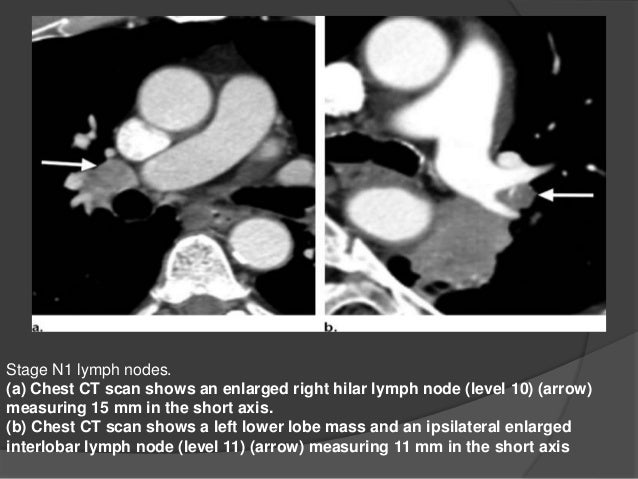

PPT - Lung Cancer Staging PowerPoint Presentation, Free Download - ID

PPT - Lung cancer staging PowerPoint Presentation, free download - ID www.slideserve.com

cancer tumor staging lung t1 carina 3cm 2cm ppt powerpoint presentation bronchus 7cm